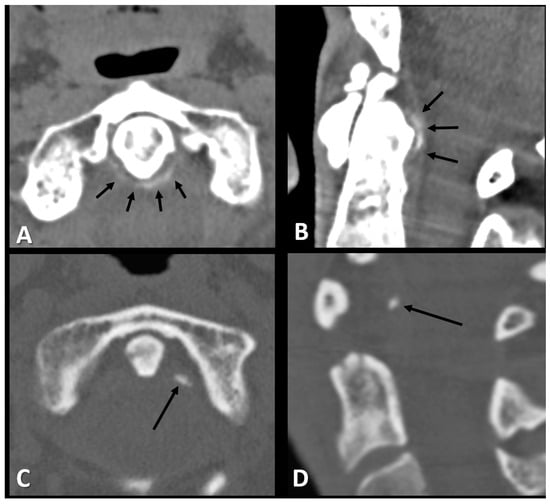

CT Examination and Evaluation